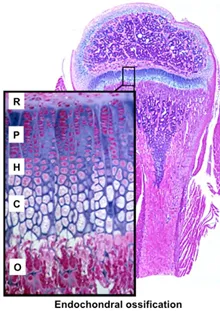

- Endochondral Ossification:

- Hyaline cartilage model replaced by bone.

- Forms most bones (long bones, vertebrae).

- Primary center (diaphysis), secondary (epiphyses).

- Length (Interstitial): Occurs at epiphyseal growth plates.

- Zones (epiphysis to diaphysis): Resting, Proliferation, Hypertrophy, Calcification, Ossification.

- 📌 Mnemonic (Zones): Real People Have Career Options (RPHCO).